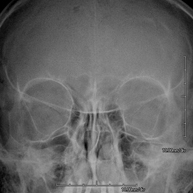

- Paranasal Sinuses X-ray

This technique uses X-ray rendered imaging for examining the paranasal sinuses. Indicated for: difficulty breathing through the nose, chronic cough, headache, mucus.

- Skull X-ray

This technique uses X-ray rendered imaging for examining the skull. Indicated for: trauma, premature cranial suture closure.